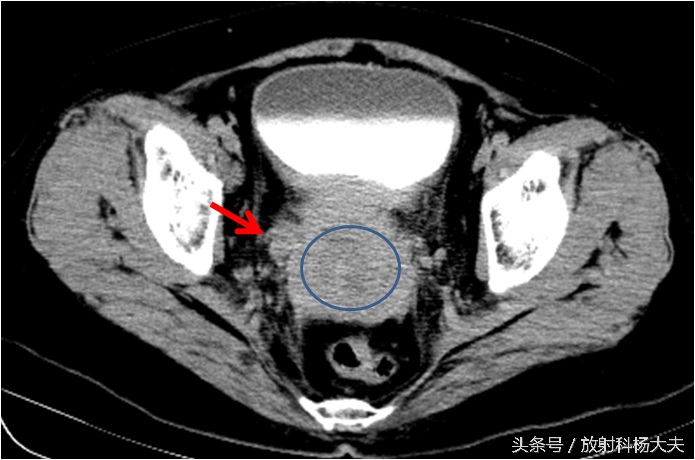

如下图就是宫颈的巨大肿瘤(圆圈所示),侵犯了右侧输尿管(红箭)。

引起了右肾积水。